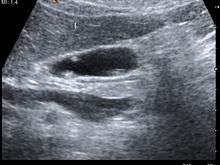

| A polyp in the gall bladder as seen on ultrasound | |

Diagnosis is typically by ultrasound or CT imaging.